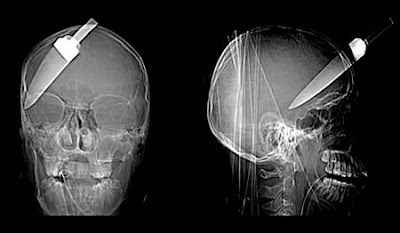

The Most Bizarre X-Rays

X-ray images show how a teenage boy cheated death when a 5-inch knife was plunged into his head. The 16-year-old and two other young men were injured when they tried to stop a friend getting robbed at a bus stop. The teenager was rushed to hospital with the kitchen knife still stuck in his forehead after the attack in Walworth, south London, in September 2008.